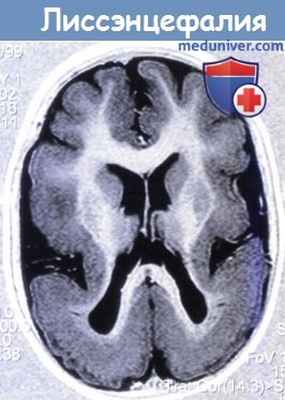

Субкортикальная гетеротопия: лиссэнцефалия

Аномалии развития головного мозга – синдром «двойной коры»

Наиболее показательным вариантом аномалии развития головного мозга является вариант ламинарной гетеротопии, когда слои гетеротипированных нейронов располагаются в глубоких и субкортикальных отделах головного мозга, известный как синдром «двойной коры».

Синдром «двойной коры» – это редкая, генетически обусловленная аномалия развития центральной нервной системы. Ее возникновение связано с мутацией гена даблкортина, локализованного в хромосоме Xg22, которая приводит к формированию ламинарной (ленточной) подкорковой гетеротопии нейронов. Вследствие подобного нарушения миграционных процессов создается иллюзия дублирования коры – «двойная кора» 3. Синдром впервые описан H. Jakob в 1936 г. и в дальнейшем выявлен S. Ricci и A Palmini у больных с эпилептическими синдромами [6]. В клинической картине синдрома наиболее часто наблюдаются задержка психомоторного развития, терапевтически резистентная эпилепсия с преобладанием парциальных/астатических приступов и дебютом припадков преимущественно после 5 лет, четкие очаговые изменения на электроэнцефалограмме (ЭЭГ), могут также встречаться инфантильные спазмы в анамнезе. Лечение этого синдрома симптоматическое, основой которого является противоэпилептическая терапия [1, 6].

Лентовидная гетеротопия, или синдром двойной коры, проявляется четко очерченным лентовидным слоем нейронов, отделенным от коры полосой белого вещества. Диагностировать данную патологию можно только по данным МРТ. При этом на изображениях выявляется ровная, четко очерченная полоса серого вещества, расположенная параллельно боковому желудочку и отделенная от коры и стенки желудочка слоем серого вещества. Кора мозга может быть неизмененной либо может быть изменена от умеренно выраженной пахигирии до полной агирии (рис. 3.21). В белом веществе на Т2-ВИ могут определяться очаги гиперинтенсивного сигнала. Лентовидную гетеротопию достаточно сложно дифференцировать с лиссэнцефалией: они, вероятно, представляют собой различные степени одного общего процесса нарушения миграции нейронов. В отличие от лиссэнцефалии, при лентовидной гетеротопии изменения коры выражены меньше.